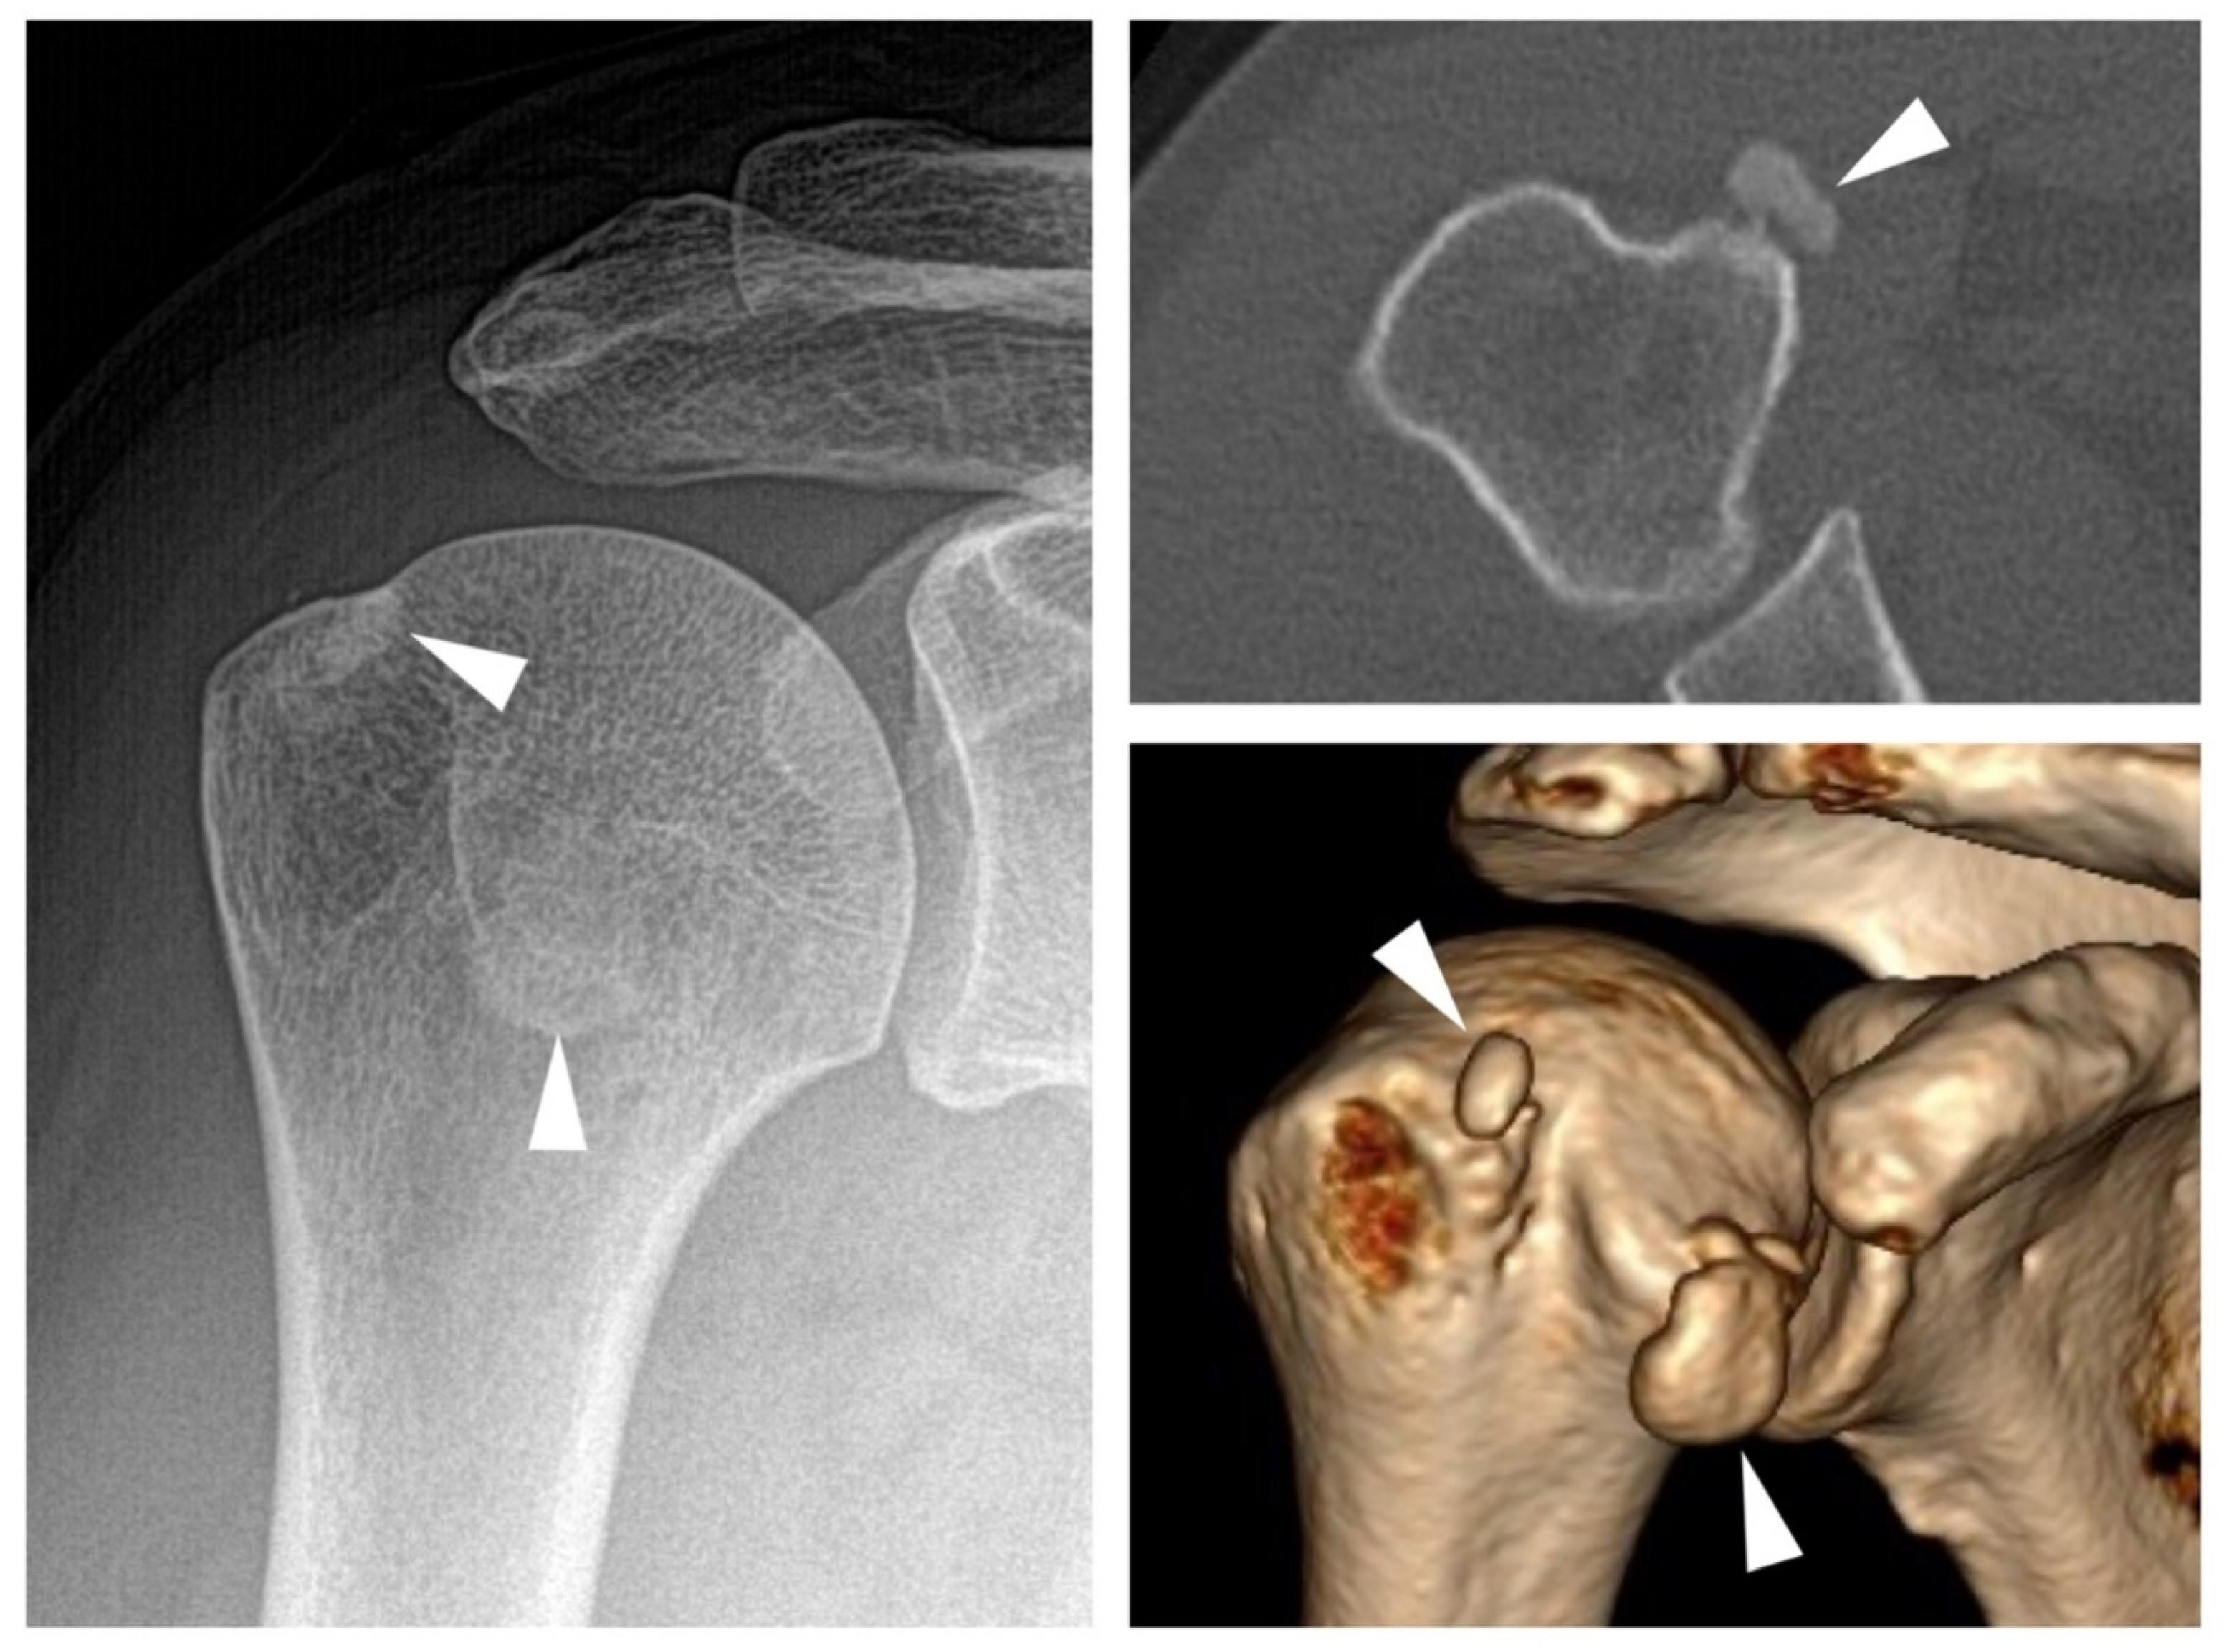

- Hongsmatip, P.; Cheng, K.Y.; Kim, C.; Lawrence, D.A.; Rivera, R.; Smitaman, E. Calcium hydroxyapatite deposition disease: Imaging features and presentations mimicking other pathologies. Eur. J. Radiol. 2019, 120, 108653. [Google Scholar] [CrossRef] [PubMed]

- Chianca, V.; Albano, D.; Messina, C.; Midiri, F.; Mauri, G.; Aliprandi, A.; Catapano, M.; Pescatori, L.C.; Monaco, C.G.; Gitto, S.; et al. Rotator cuff calcific tendinopathy: From diagnosis to treatment. Acta Biomed. 2018, 89, 186–196. [Google Scholar] [PubMed]

- Jacques, T.; Michelin, P.; Badr, S.; Nasuto, M.; Lefebvre, G.; Larkman, N.; Cotten, A. Conventional Radiology in Crystal Arthritis. Radiol. Clin. N. Am. 2017, 55, 967–984. [Google Scholar] [CrossRef] [PubMed]

- Cho, N.S.; Lee, B.G.; Rhee, Y.G. Radiologic course of the calcific deposits in calcific tendinitis of the shoulder: Does the initial radiologic aspect affect the final results? J. Shoulder Elb. Surg. 2010, 19, 267–272. [Google Scholar] [CrossRef]

- Uhthoff, H.; Sarkar, K. Calcifying tendinitis. Baillières Clin. Rheumatol. 1989, 3, 567–581. [Google Scholar] [CrossRef]

- Greis, A.C.; Derrington, S.M.; McAuliffe, M. Evaluation and Nonsurgical Management of Rotator Cuff Calcific Tendinopathy. Orthop. Clin. N. Am. 2015, 46, 293–302. [Google Scholar] [CrossRef]

- Ea, H.; Lioté, F. Calcium pyrophosphate dihydrate and basic calcium phosphate crystalinduced arthropathies: Update on pathogenesis, clinical features, and Therapy. Curr. Rheumatol. Rep. 2004, 6, 221–227. [Google Scholar] [CrossRef]

- McCarty, D.J. Milwaukee shoulder syndrome. Trans. Am. Clin. Climatol. Assoc. 1991, 102, 271–283, discussion 283–274. [Google Scholar]

- Santiago, T.; Coutinho, M.; Malcata, A.; Da Silva, J.A.P. Milwaukee shoulder (and knee) syndrome. BMJ Case Rep. 2014, 2014, bcr2013202183. [Google Scholar] [CrossRef] [PubMed]